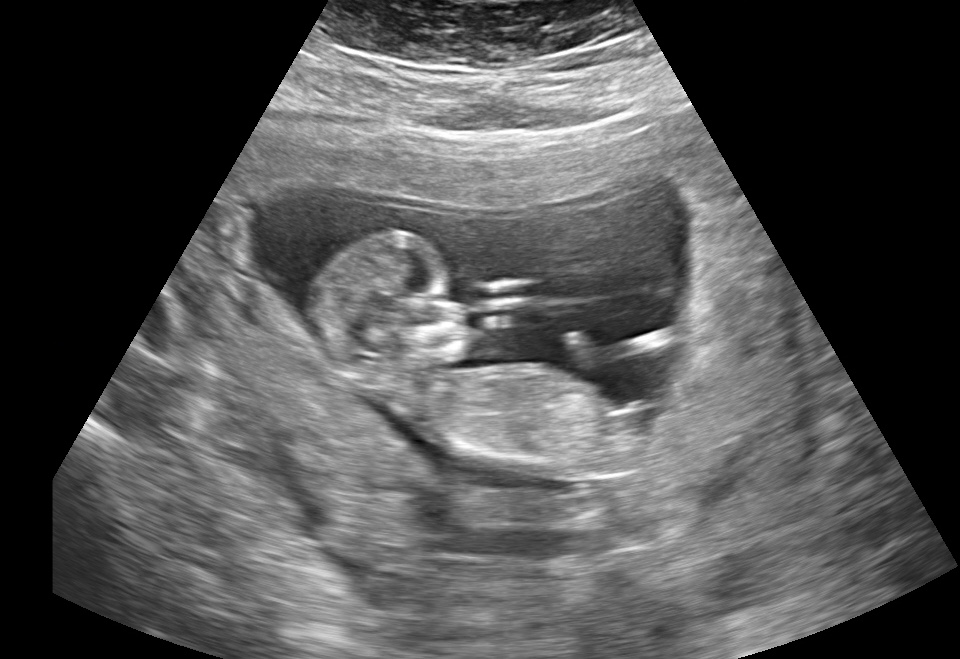

21 weken